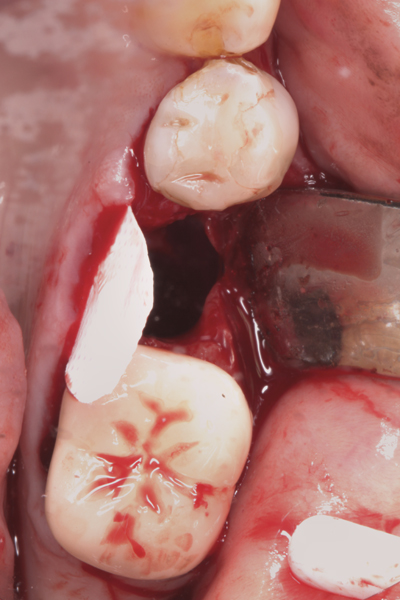

Fig 17. Bone graft was placed in the socket and a d-PTFE barrier was used to cover the graft. The bone graft material was placed beyond the alveolar housing to accommodate shrinkage of graft material and to facilitate attaining a wide alveolar ridge. The barrier was removed after 6 weeks.

Figure 17

Fig 18. Healed ridge exposed after 6 months.

Figure 18